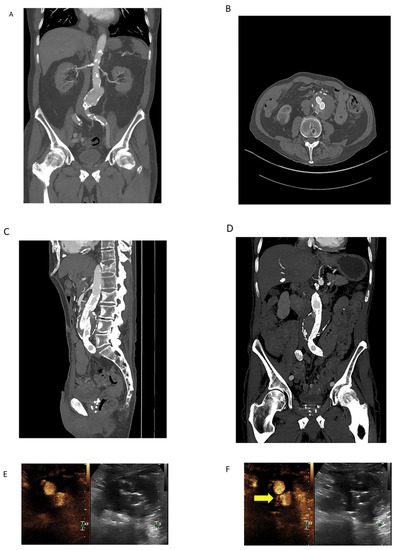

Figure 3.

Coronal MIP image (A) demonstrating an infrarenal AAA in a 78-year-old male obtained prior to endovascular repair. Calcific atherosclerotic plaque and vessel patency well-demonstrated on this arterial phase CTA. 100 mL of Omnipaque 350 contrast was administered with CTDIvol of 7.68 mGy. Arterial phase source axial image (B) from a CTA demonstrating endovascular repair of the infrarenal AAA with persistent contrast flow into the excluded aneurysm sac, consistent with an endoleak. Sagittal (C) and coronal (D) MIP images are also shown. Lack of dynamic imaging limits classification of the type of endoleak; although, it was initially characterized as a type II endoleak by CTA. 100 mL of Isovue 370 contrast was administered with CTDIvol of 5.77 mGy. Subsequent contrast-enhanced ultrasound (CEUS, (E)) with dynamic contrast enhancement demonstrated a type III endoleak arising from the origin of the left iliac limb ((F), yellow arrow). The type III endoleak represents the major component and a large portion of the bolus empties into the aneurysm sac ((G), yellow arrow) with a small type II contribution arising from a right lumbar artery (not shown). Three boluses totaling 5 mL of Lumason were injected.